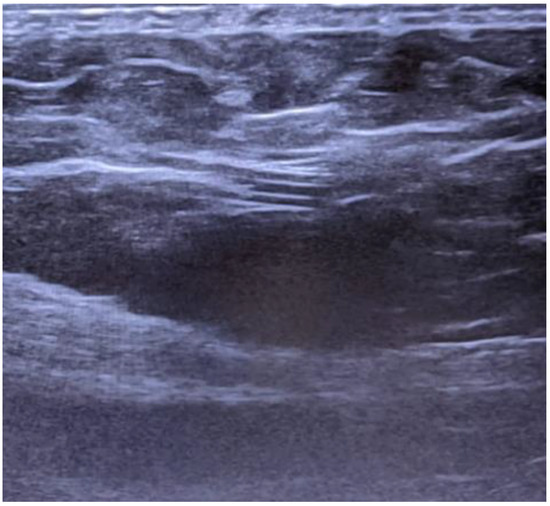

The ultrasound depicts the shunt as having a shallow trajectory from the right latero-cervical region to the epigastrium (Figure 3), from where it enters deeply, the access at the peritoneal cavity being located in the right paraumbilical area, but without being able to visualize the distal end (Figure 4). Neurosurgical consultation was subsequently performed, which recommended temporary shunt ligation. Suturing and ligation of the shunt was performed with the recommendation of ligature thread suppression 24 hours postoperatively and reassessment as needed.

Figure 3. Superficial shunt pathway in subcutaneous tissue